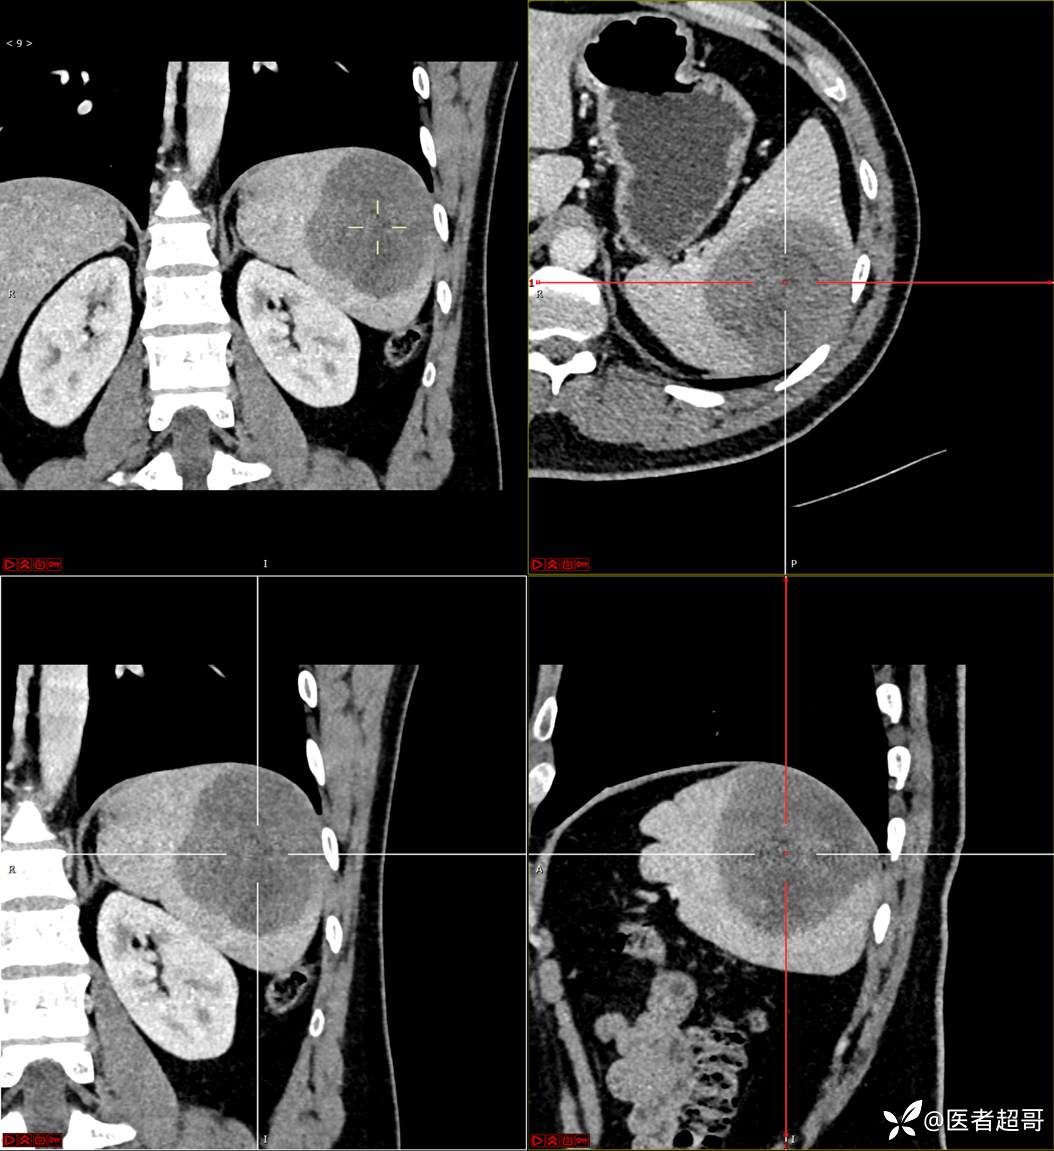

【影诊笔记596】脾脏占位01,你的病谱能网住吗?请分析,留言查询病理及术程!

主 诉:发现脾占位2月余。

现病史:患者2月余前体检彩超提示脾占位性病变,未予特殊诊治,2023.12.1于潍坊市坊子区人民医院行肝胆胰脾MR平扫提示脾脏占位性病变,左肾小囊肿,现患者无腹胀、腹泻,无恶心呕吐,无胸闷憋气等症状,今为求进一步治疗,患者来我院就诊,门诊以“脾占位性病变”收入院。患者自发病以来,一般情况可,神志清,精神可,饮食、二便正常,睡眠可,体重体力无明显改变。